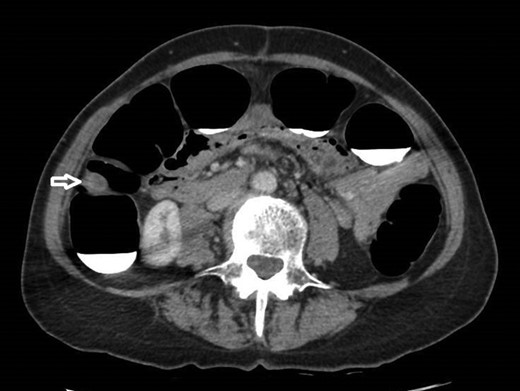

12 mm polypoidal mass (white arrow) visible on coronal image of post-contrast CTVC.

In view of this CT Colonoscopy was performed, alongside a CT Chest examination. This showed a 12 mm lesion arising from the lateral wall of the ascending colon. It appeared rounded and mural-based, and displayed irregular peripheral enhancement post-contrast. It did not conform with a lipomatous lesion, with an average internal density of approximately 40 HU. No other colonic lesions were demonstrated, and no locoregional adenopathy or distant metastases were identified.